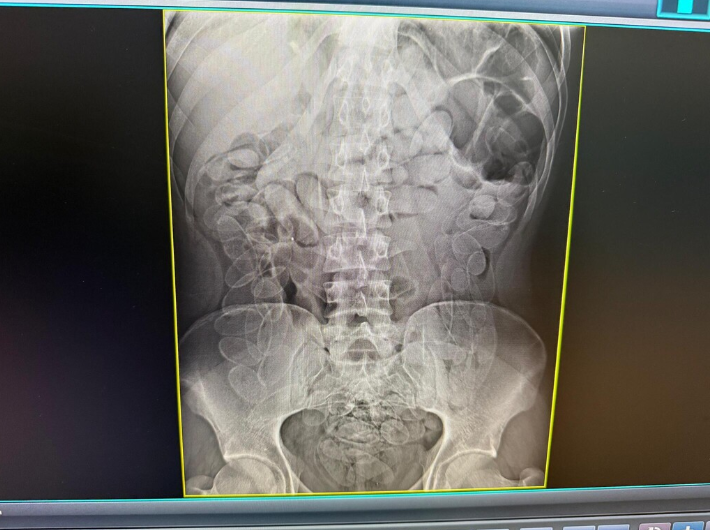

Exame de raio-x mostra cápsulas de cocaína no estômago de um rapaz em 2025 (Foto: Ilustrativa | Divulgação)

Ainda segundo o boletim de ocorrência, a mulher afirmou ter ingerido as cápsulas em território boliviano há cerca de sete dias e que permaneceu com o material no organismo durante todo esse período. Um exame de raio X da região abdominal revelou múltiplos invólucros no estômago.